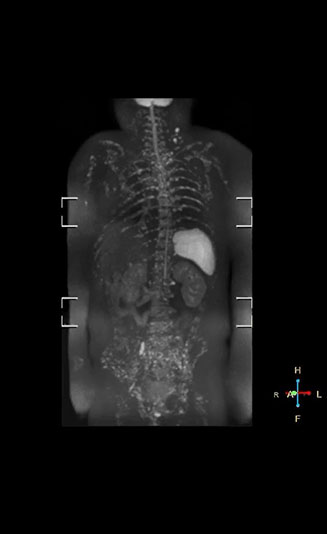

“With coronal DWIBS, we can perform a full whole body exam, including other sequences, within 30 min.”

Coronal DWIBS is faster and improves image quality

“Switching to coronal DWIBS – rather than axial – further shortens scan time,” says Mr. Naka. “Important is that a dS SENSE factor of 5 shortens exam time while high image quality can be maintained, thanks to Ingenia’s dStream architecture.” He adds that the coronal orientation also avoids artifacts that are specific to combining axial images.

“When we use a coronal DWIBS acquisition, we can perform a full whole body examination, including other required sequences, within 30 minutes,” he says.

“This is considerably faster than the previously used exam with axial whole body DWI, which took more than 45 minutes,” he notes. “A shorter exam is more patient-friendly and allows us to also use it on patients in poor health who would have difficulty tolerating a long exam. Limiting the exam time is also helpful for scheduling, because it fits in a normal single exam timeslot.”

Kawasaki Sawai Hospital’s whole body protocol also includes an mDIXON FFE sequence. Because mDIXON provides images for four contrast types – water only, fat only, in-phase and out-of-phase – from a single acquisition, it is useful in many ways.